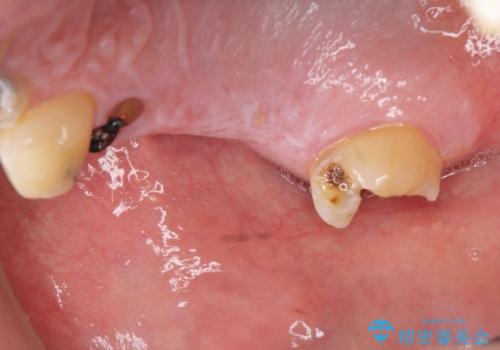

- 「 仕事が忙しく、虫歯を放置しすぎてしまった。この際全てきっちりと治したい。」と来院されました。

・歯の欠損

・虫歯

・深い虫歯

以上のような問題を、徹底的な虫歯治療、歯周外科、インプラント治療、部分矯正治療、精密根管治療を用いてひとつずつ解決ししっかりと長期的に食事を楽しめるような口腔内環境の再構築を目指します。